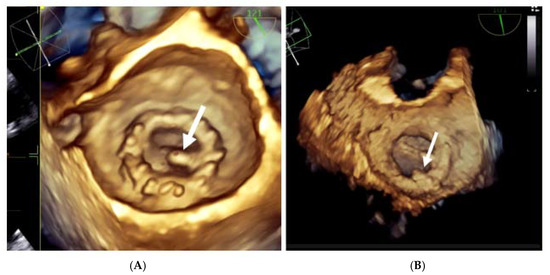

Three-dimensional real-time echocardiography (RT3DTEE) brings new perspectives in the evaluation of thrombosis on cardiac prostheses because of its superior imaging quality [36,37,38,39].

When accessible, 3D TEE is advised because it might identify prosthetic thrombi that 2D TEE misses or only partially detects [36].

The ability to identify thrombosis is improved by 3D en face reconstruction of the prostheses.

In comparison to 2D TEE, RT3DTEE provides a more accurate visualisation of the mechanical valve structures such as leaflets, rings, and struts. Leaflet restriction, softer echo density, higher mass, and quick gradient development across the valve are variables that favour thrombus over pannus. Three-dimensional TEE can also section the echogenic mass and visualize it from multiple angles, allowing the presence, extension, and localization of thrombus, pannus, or vegetation to be distinguished [40].

Moreover, 3D acquisitions can assist with the detection of silent thrombi that are present at the level of the prosthesis’ ring (Figure 8, panel B). In nonobstructive thrombi, where it is required to intensify anticoagulation and conduct rigorous monitoring, 3D TEE has a higher diagnostic value than 2D TEE [23,24,25,36,37,38,39].

Figure 8.

3D TEE with en face reconstruction of the mechanical mitral prosthesis with thrombus. (A) On disc (arrow). (B) On ring (arrow).